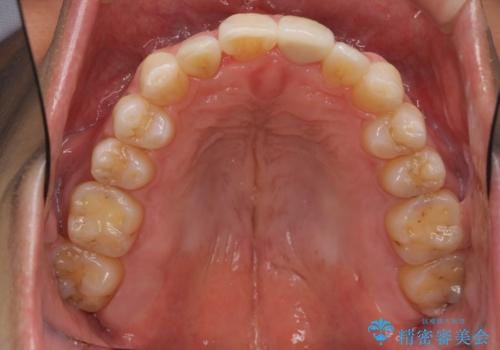

- 前歯の重なったところが虫歯になり、物理的にアプローチが難しい状態でした。

矯正治療前に虫歯を取り、歯並びが良くなってから本格的にセラミック治療を行いました。

左上1はジルコニアクラウン(スペシャル)で治しました。スペシャルの場合は写真をとり、オリジナルの色味で作成することが可能です。